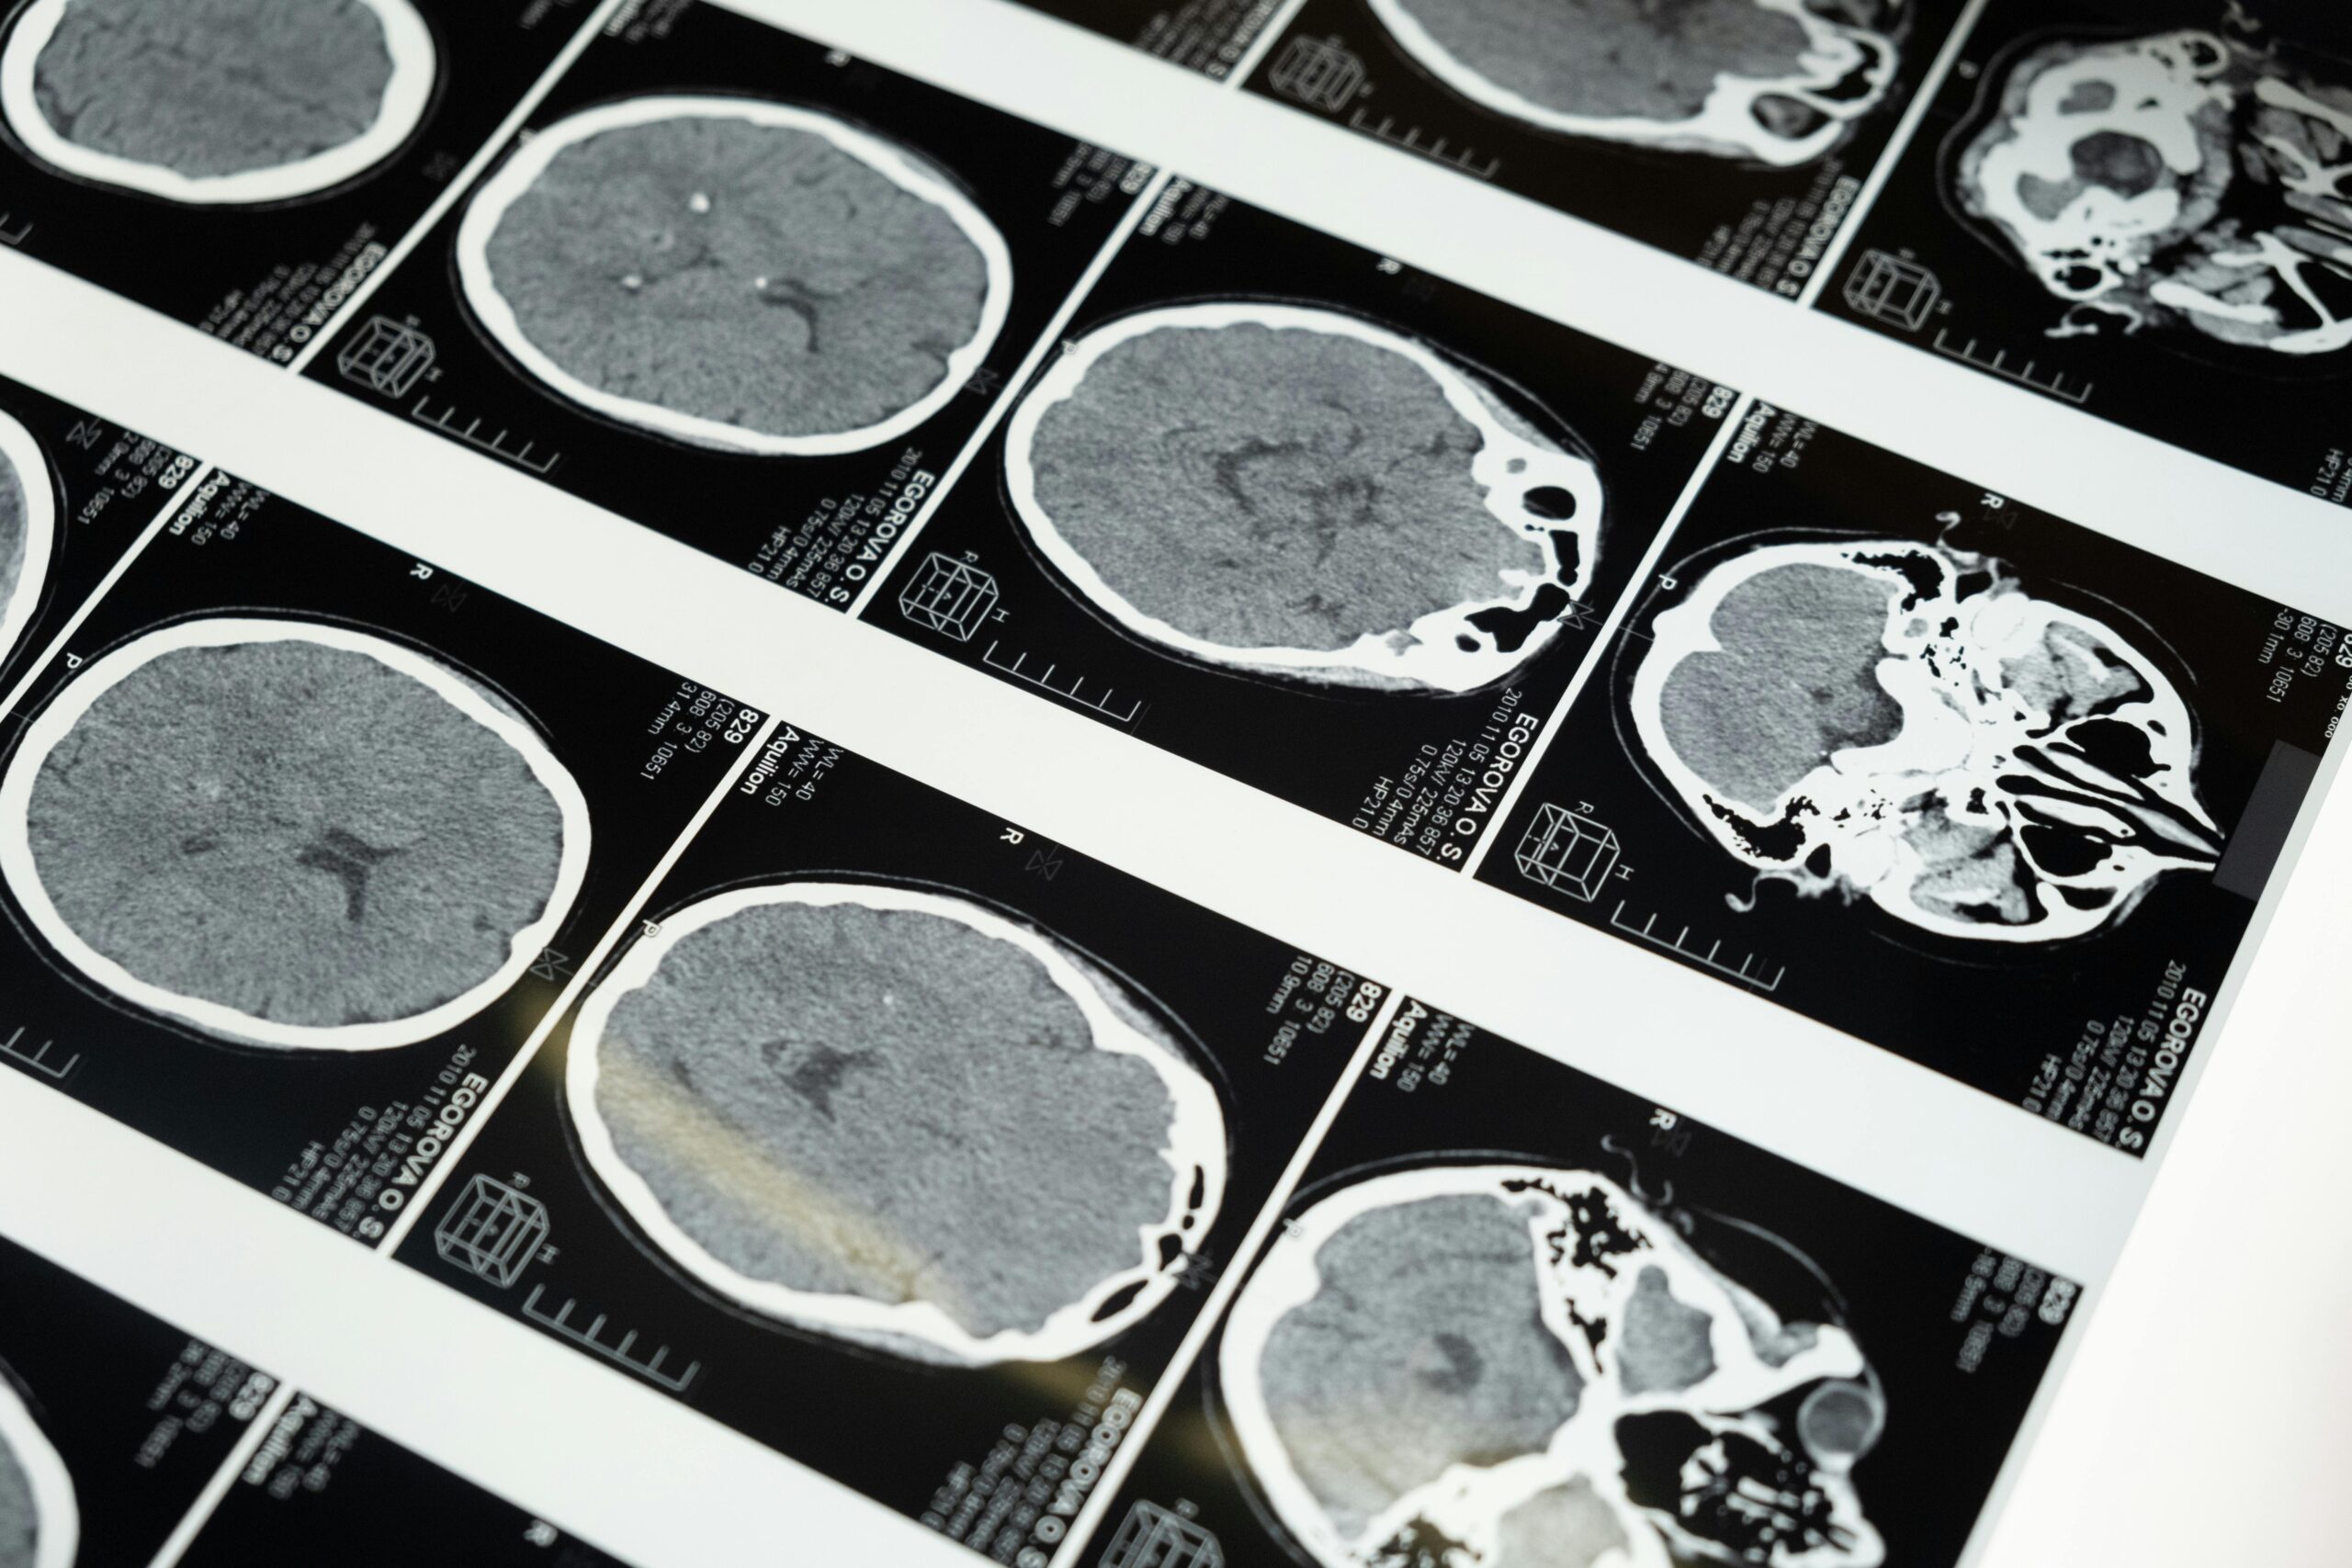

Detailed brain MRI scans displayed on a lightbox, showcasing medical imaging techniques.